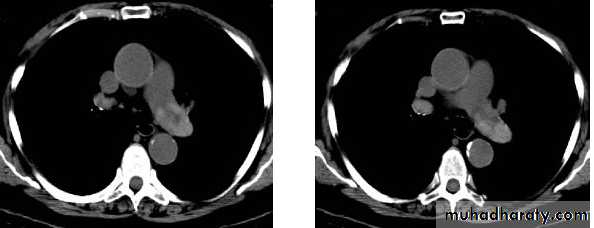

1- presence and extent of med. Masses and other abn.: demonstrate LNs enlargement

Distinguish vascular from non vascular structure: e.g. mass from aneurysm.

CT allows fat to be recognized e.g.: Dx fatty tumors or excluding med. Widening due to merely excess fat deposition.

NECT with lt. pulm. A. thrombosis2- Showing shape of intrapulmonary or pleural opacity, detecting calc. or cavitation when plain CXR not conclusive.

7- pulm. embolism.